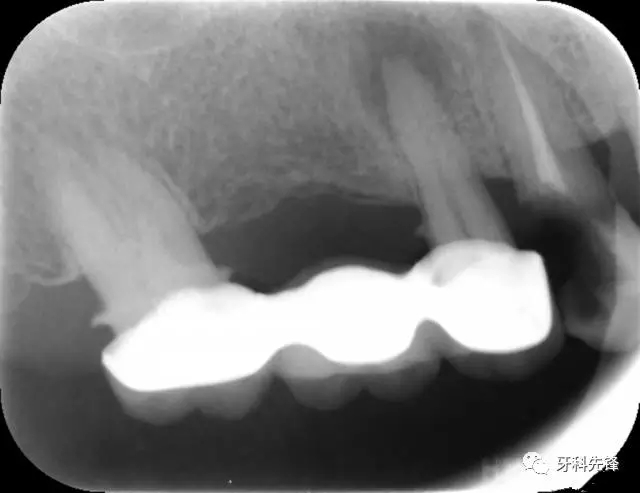

X 示:15  根管透射,根尖有陰影

14  根管阻射,恰填,無異常

46  根管阻射,恰填,根分叉骨密度降低,近中根尖陰影較大

圖8治療術后X光片